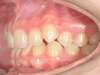

Chevauchement sévère. Traitement multibague sans extraction.

Avant

Après